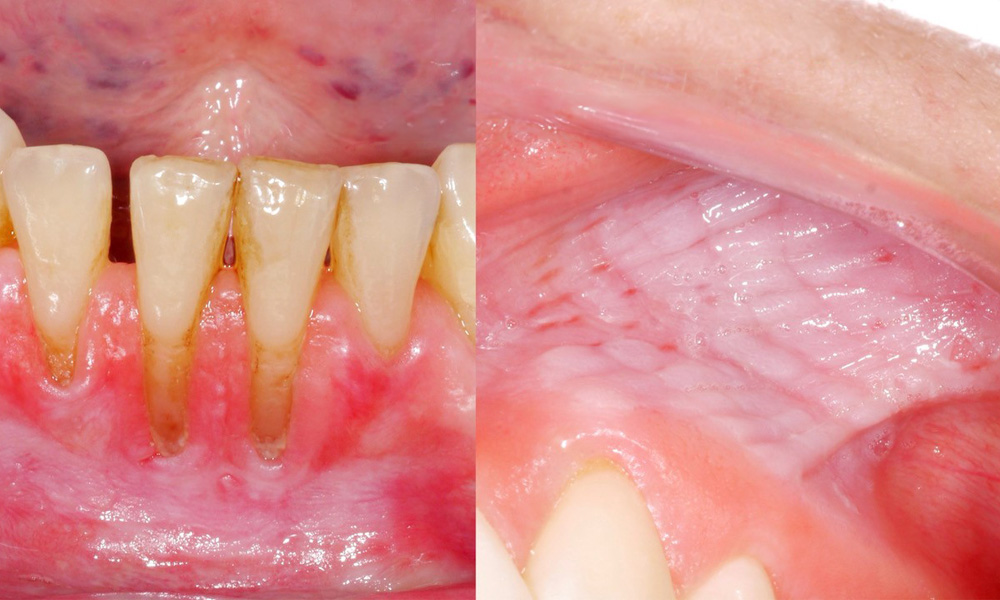

The clinical examination showed that regular consumption of snus can have the following effects on the oral mucosa:

- Approximately 80% of those examined who consumed snus daily had snus-induced mucosal lesions.

- Approximately 20% of those examined who consumed snus daily had snus-induced gingival recession.